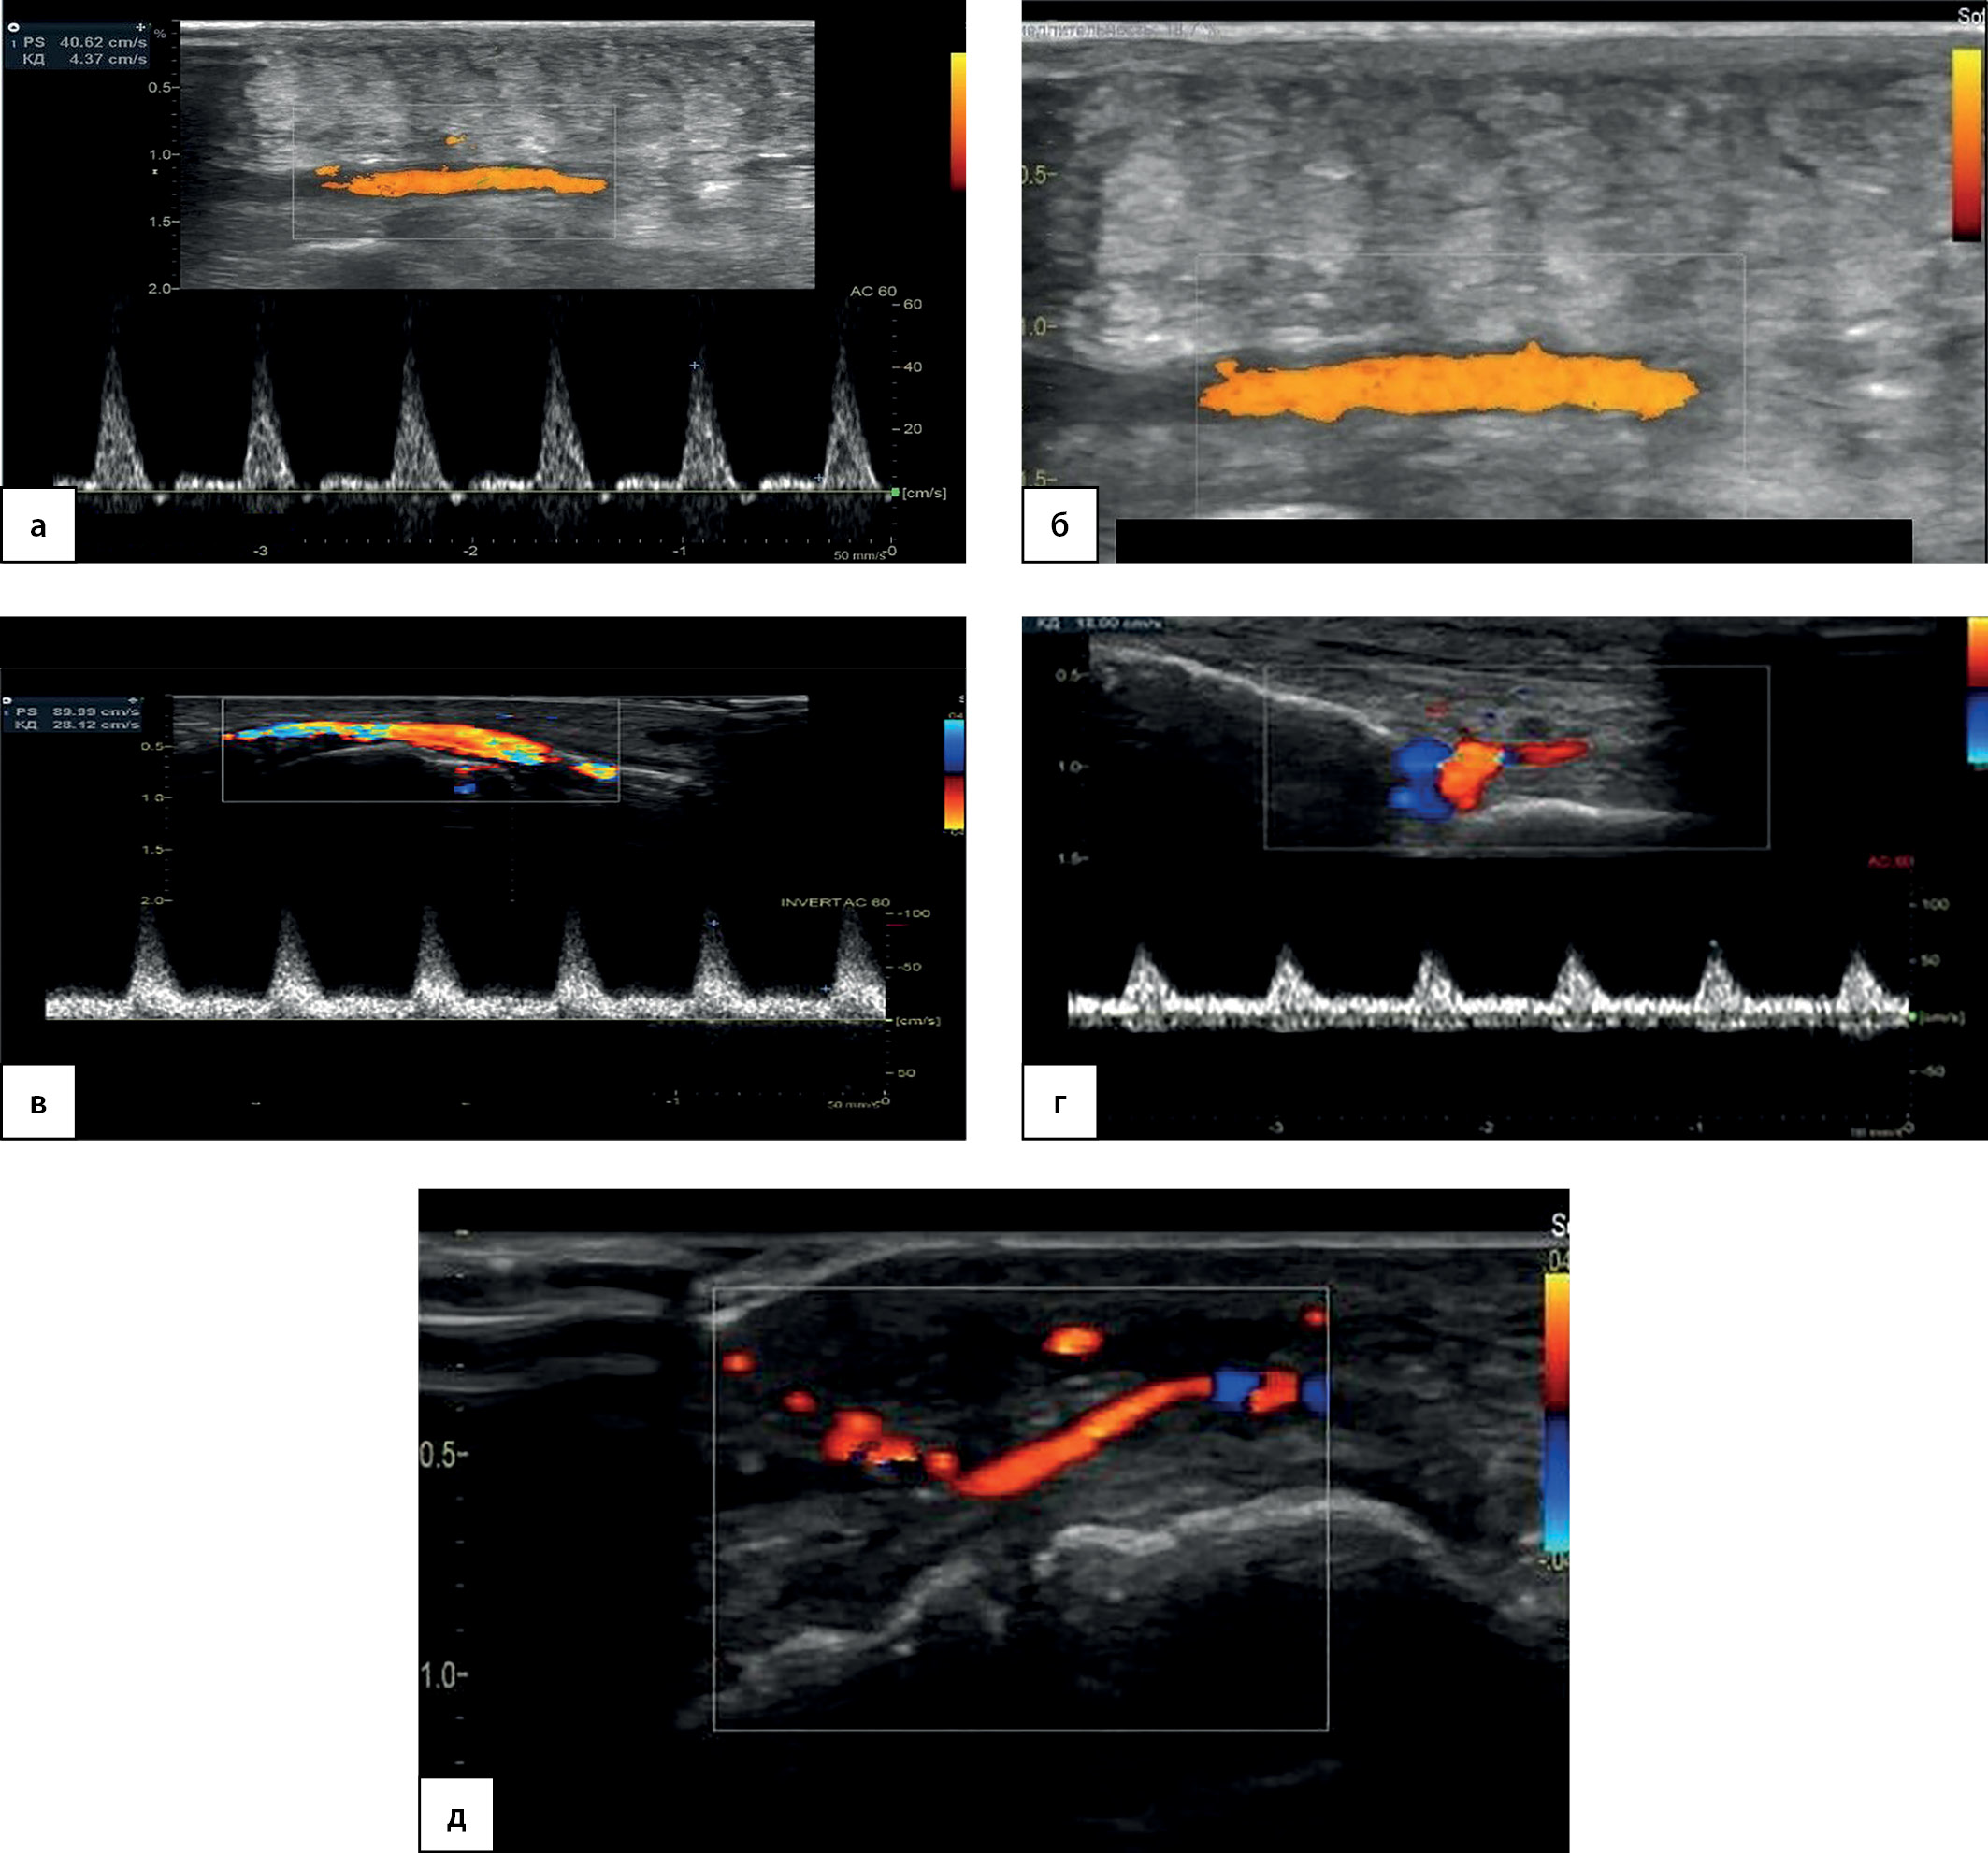

При контрольном УЗДС артерий 29.08.2022 г. отмечено восстановление кровотока по ЗББА, ЛПА, МБА и ТАС с остаточными стенозами по артериям голени до 50–60%. Регистрируется магистральный кровоток по ТАС, восстановление просвета и магистрально-измененного кровотока по ЛПА, а также по тыльным и подошвенным плюсневым артериям в 3–4 межфаланговых промежутках с оптимальной визуализацией их просвета (рис. 7).

Рисунок 7. Контрольное ультразвуковое дуплексное сканирование

артерий нижних конечностей.

а — Магистральный кровоток с низким периферическим сопротивлением по тыльной артерии стопы, прирост пиковой систолической скорости кровотока — с 56 до 89 см/с. Режим цветового допплеровского картирования, дополненный допплерографией.

б — Латеральная подошвенная артерия, равномерное окрашивание просвета. Режим энергетического допплеровского картирования, дополненный допплерографией.

в — Магистральный кровоток по латеральной подошвенной артерии, пиковая систолическая скорость кровотока — 40 см/с. Режим энергетического допплеровского картирования, дополненный допплерографией.

г — Магистрально-измененный кровоток по тыльной плюсневой артерии в 4-м плюсневом промежутке, прирост пиковой систолической скорости кровотока — с 15 до 66 см/с. Режим цветового допплеровского картирования, дополненный допплерографией.

д — Подошвенная плюсневая артерия в 4-м плюсневом промежутке после реваскуляризации. Режим цветового допплеровского картирования.